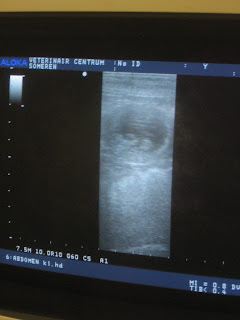

Maar de rit was echt niet voor niks geweest, want nadat de scanner op haar buikje gezet werd, zagen we meteen een gevuld vruchtblaasje op het scherm, en nog een, nog een en uiteindelijk zijn we gestopt met tellen bij 5 stuks.

Hieronder een aantal foto's die ik met mijn eigen camera heb gemaakt, want de printer van de praktijk wilde even niet meewerken...